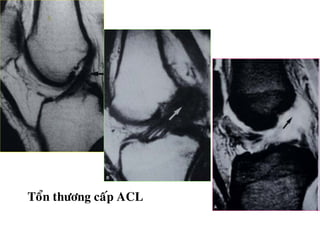

TOÅN THÖÔNG DAÂY CHAÈNG CHEÙO

- Daây chaèng coù höôùng ñi baát thöôøng, maát lieân tuïc moät

phaàn, coù tín hieäu dòch cao treân T2W beân trong, daây

chaèng phuø daøy leân (toån thöông caáp) hay khoâng daøy (toån

thöông maïn).

Toån thöông caáp ACL

TOÅN THÖÔNG DAÂYCHAÈNG CHEÙO - Daây chaèng coù höôùng ñi baát thöôøng, maát lieân tuïc moät phaàn, coù tín hieäu dòch cao treân T2W beân trong, daây chaèng phuø daøy leân (toån thöông caáp) hay khoâng daøy (toån thöông maïn). - Maát lieân tuïc hoaøn toaøn, khoâng thaáy daây chaèng treân phim.